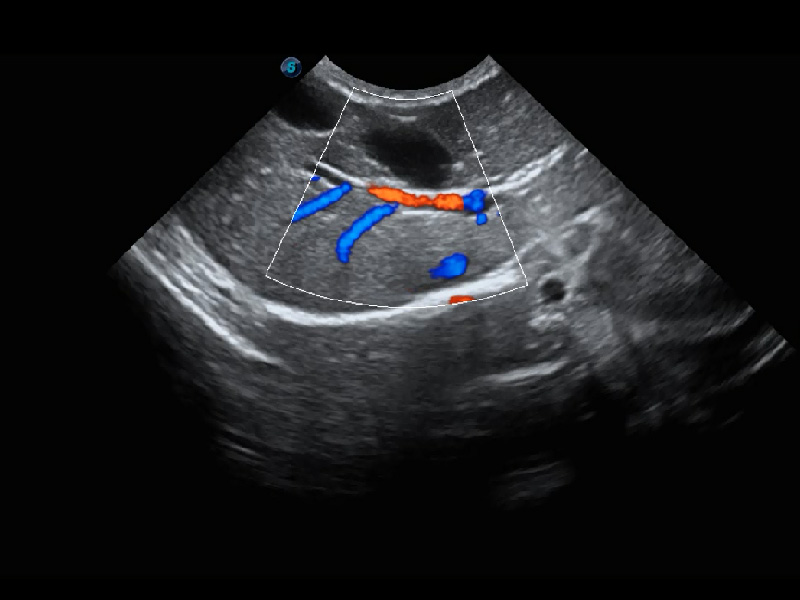

ProPet 60 作为一款高端台式动物超声设备,为动物医生的日常诊断提供了一系列贴合动物临床需求、解决临床实际问题的高级成像功能。凭借全系列高清探头,满足医生对腹部、心脏、生殖、浅表、肌骨等成像的所有需求,切实帮助您提升检查效率,提高诊断信心。

ProPet 60 尊享版

兽用彩色多普勒超声诊断系统